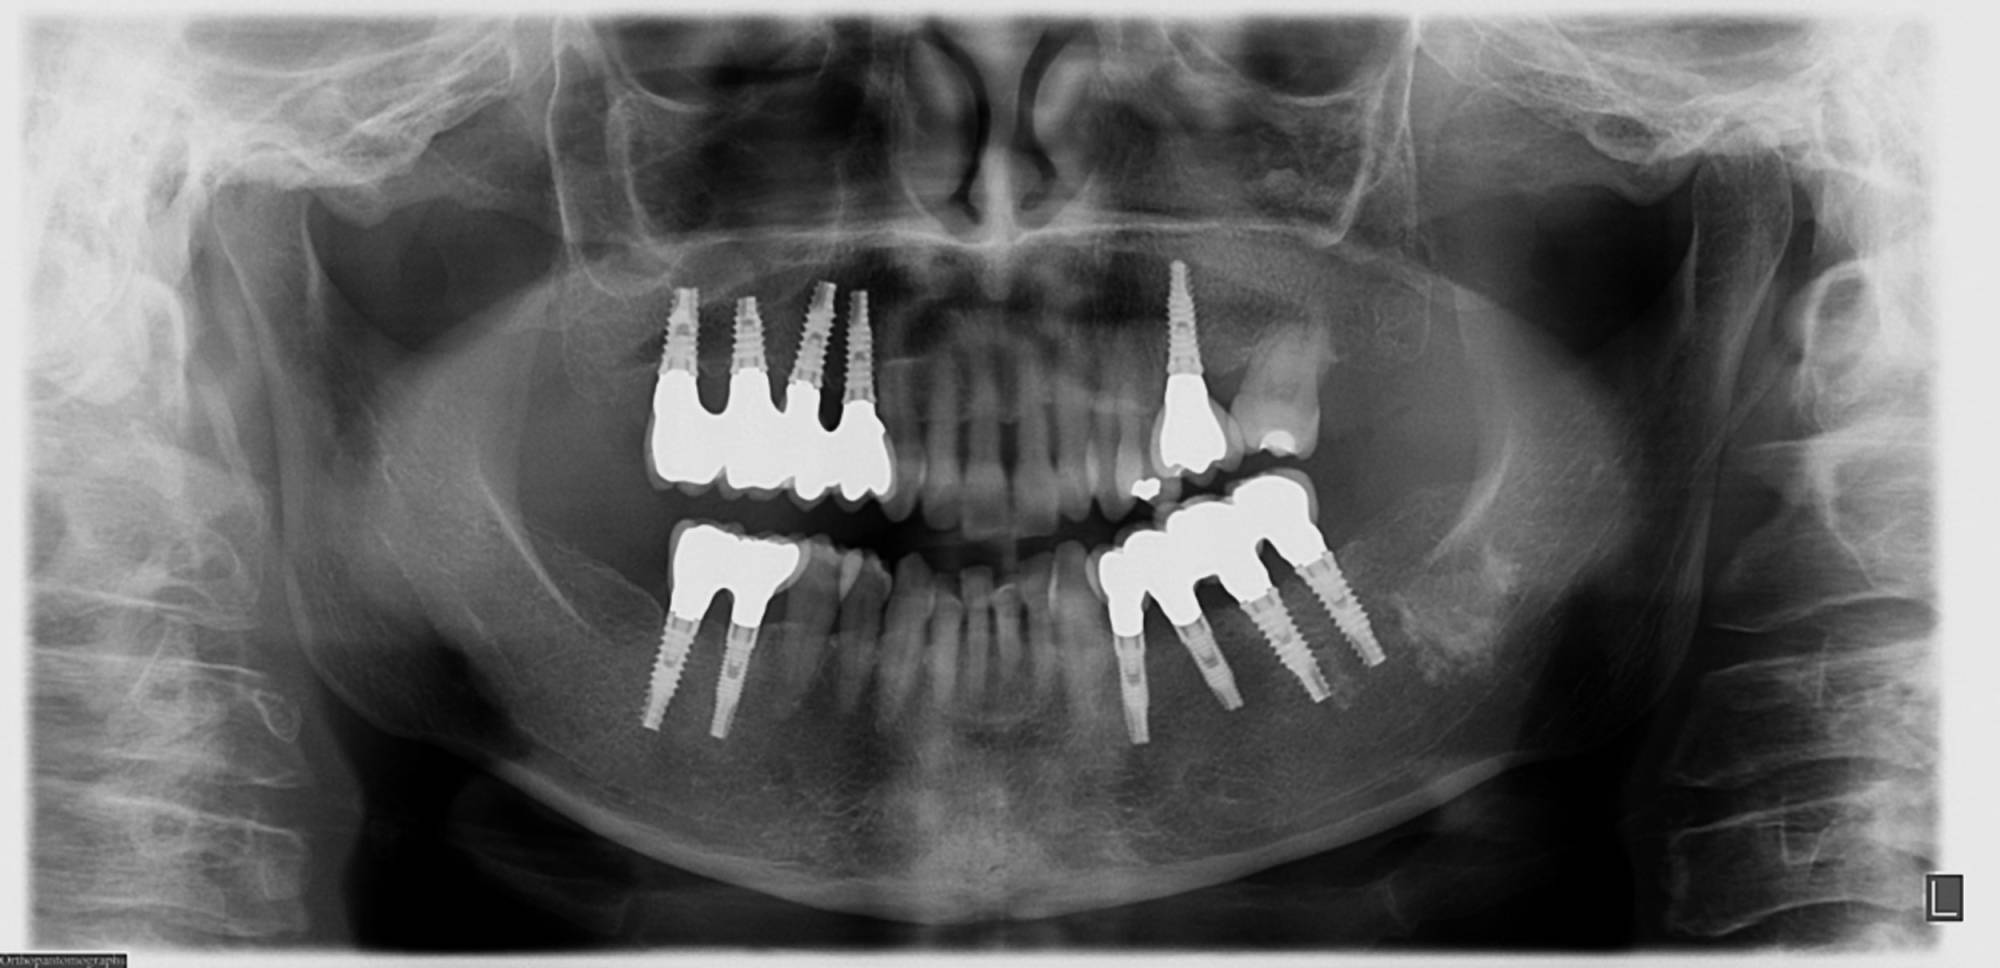

Una tecnica recente e molto apprezzata è l’implantologia computer guidata. L’anatomia della zona da operare è studiata con la Tomografia Computerizzata, simulando al computer, con un software di alta precisione 3D, il posizionamento degli impianti. Sulla base dei dati elaborati dal software si realizza in laboratorio una mascherina chirurgica che guiderà gli strumenti e gli impianti nella corretta posizione nell’osso del paziente, rendendo l’intervento più sicuro e veloce.